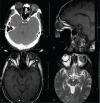

Diagnoses: Preoperative B-scan, color fundus photography, computed tomography, and magnetic resonance imaging showed a choroidal tumor in his left eye. The spontaneous rupture of the corneoscleral limbus from 2 to 5 o'clock, combined secondary glaucoma, exudative retinal detachment and choroidal detachment were found.